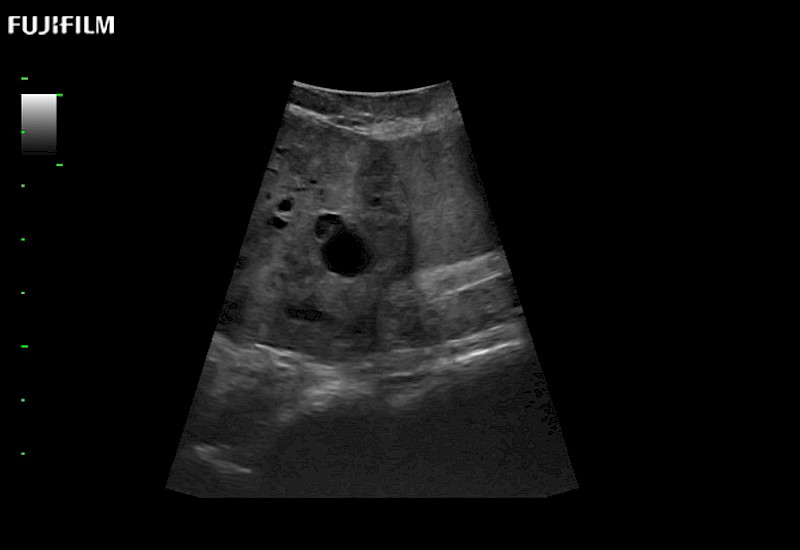

Exclusive linear array 4-way laparoscopic transducer for better visualization of targeted lesions.

Main Specifications:

Exclusive linear array rigid laparoscopic transducer for better visualization of targeted lesions.